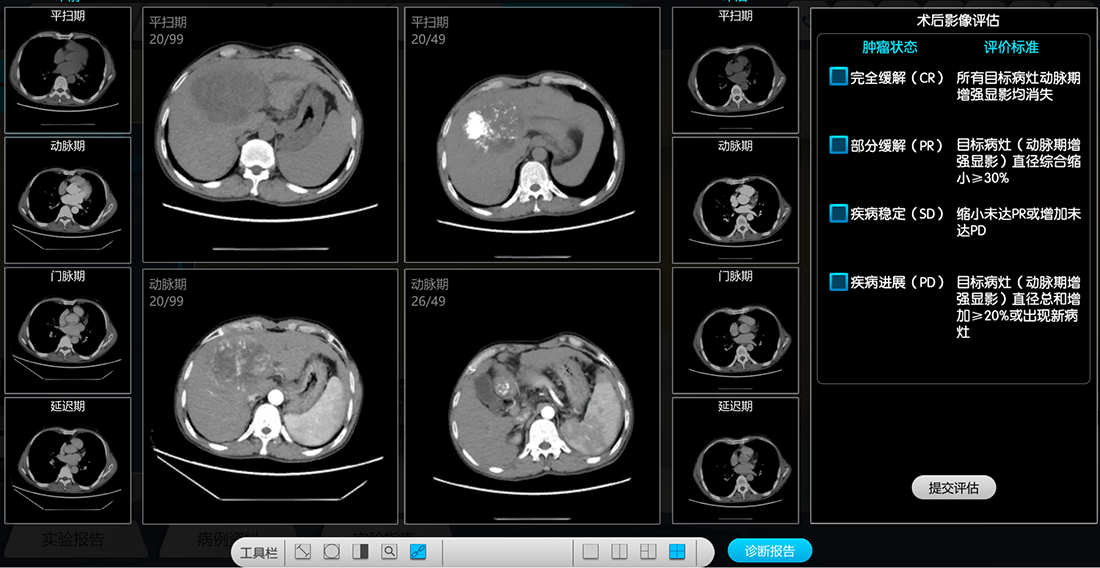

项目围绕“肝癌病理特征”这一底层原理知识点,建立“诊断—治疗—评估”完整临床诊疗环路。①诊断:肝癌血供大部分来自于肝动脉,在CT/MR增强扫描过程中,肝癌病灶显影方式异于正常肝组织而呈现“快进快出”状态,依据这一影像特征可辅助疾病诊断。②治疗:基于肝癌的特殊血供,肝动脉化疗栓塞术(TACE)过程中通过导管导丝配合控制,可以精确进入肿瘤供血动脉并注入化疗栓塞药物,堵塞肝癌的营养血管使其坏死萎缩,达到治疗作用。③评估:国际最新mRECIST标准规定肝癌治疗效果主要依赖于影像学评估,通过判断介入治疗效果、分析深化,明确下一步治疗方案,完成诊疗环路。项目采用“四模块-四层次”的设计思路(图 1):涵盖“患者接诊”“影像诊断”、“介入手术”、“术后评估”等四个模块,构思了“认知-分析-综合-深化”递进式的实验层次,将育人元素贯穿始终,注重培养学生思想品德、社会责任、工匠精神、医学伦理、职业素养。实验各模块是临床诊疗环路中的重要步骤,相互紧密联系、环环相扣,对培养学生诊疗一体化综合思路具有重要作用,最终实现项目制定的能力和素养培育目标。

本项目综合采用观察法、比较法、控制变量法、自主设计法等实验方法,使学生全面掌握影像扫描的原理和方法、肝脏解剖结构以及肝癌的发病机制、临床表现、影像诊断、鉴别诊断及介入治疗原则和方法。1)观察法 主要应用在“患者接诊”中患者的基本病史、一般状况、体格检查的环节和“影像学评估”中患者影像资料的观察分析。通过接诊过程中的各项观察了解患者的阳性症状、体征等信息。通过观察患者的影像资料对CT/MRI检查图像有感性的认知。2)比较法 主要用于“影像学评估”中肝癌病灶于CT平扫、动脉期、门脉期、平衡期不同时期密度的对比,判断病灶的血供及清退情况,学生可以纵向的掌握肝癌影像学评估过程的CT强化特点等相关知识点,符合学生的学习认知规律。比较法也用于“介入手术”中治疗前、治疗后血管造影的对比,判断治疗是否达到预期效果。在“术后影像学评估”环节中,通过对比术前、术后的CT/MR图像,学生可以应用国际公认的肿瘤缓解标准认知、判断的肿瘤治疗前后变化,符合学生的学习认知规律。3)控制变量法 主要用于CT扫描过程,学术应固定扫描的方式等全部参数,通过控制CT扫描时间节点,获取高质量的影像图像。可以让学生详细了解某个参数对成像质量的影响。在介入手术过程中,固定导管位置、对比剂每秒注入量,改变对比剂注入总量,可获得不同的血管造影表现,让学生对对比每秒注入量、注入总量等参数有深刻认识,培养学生的探究思维及科研素质。4)自主设计法 主要用于介入治疗血管插管环节,提高学生学习的主动性和积极性,同时有助于培养学生的创新意识。血管插管过程为开放式环境,导管可采用多种路径,并可选至任意血管,最终达到靶血管为实验目的。学生可自主探究设计最优的插管路径,让学生深度参与介入手术的过程,最终得到满足设计目标而最高效的设计方案。

本虚拟仿真项目总体采用“三阶段、四模块、四层次”的设计思路,分层次、递进式、螺旋式地对学生的学习效果进行各方面能力考核,“三阶段”具体分为“预习阶段”、“探究阶段”和“总结阶段”考核, “四模块”涵盖“患者接诊”、“影像学评估”、“介入手术”、“术后评估”四大模块,“四层次”构思了“认知-分析-综合-深化”递进式的四级层次,总分为100分。1)预习阶段考核——预习考核是在学生掌握相关知识背景之后、正式进行虚拟仿真实验之前进行的。该阶段考核的目的是考察学生的自主理论学习能力,判断学生是否有足够的知识储备进行虚拟仿真实验,从而保证虚拟仿真实验的效果。形式为10道选择题,每题1分,满分10分。本阶段考核成绩在最终考核成绩中占10%。2)探究阶段考核——探究阶段考核分为患者接诊、影像学评估、介入治疗、术后影像评估四大模块,该部分目的是为了使学生全面掌握相关知识点,判断学生是否按照标准流程进行实验、是否对实验现象和实验结果有清晰的认识,学生在探究模块必须完成足够的实验步骤并按四大模块有条理地进行实验操作。“患者接诊”模块主要考核学生病史采集能力、系统、规范地进行体格检查的能力和检验分析能力,“影像学评估”模块主要考核学生的影像扫描技术能力、对比剂应用能力和影像资料分析及报告书写能力,“介入治疗”模块主要考核学生的介入治疗处理能力,“术后影像评估” 模块主要考核学生的肿瘤缓解评估能力和根据具体情况选择最适合且经济的诊断、治疗手段的综合分析能力。形式以“勾选式”为主,细分选项分值设置在1-5分不等,错选、漏选不得分,满分80分,四模块分值占比为1:3:3:1,本阶段考核成绩在最终考核成绩占80%。3)总结阶段考核——该阶段内容在学生已完成前2个阶段考核后进行,主要考核学生对实验结果、结论的分析总结能力,用循证医学的原理,针对临床问题进行查证、用证的初步能力。以心得体会及其他内容拓展为主要形式,满分10分,本阶段考核成绩在最终考核成绩中占10%。